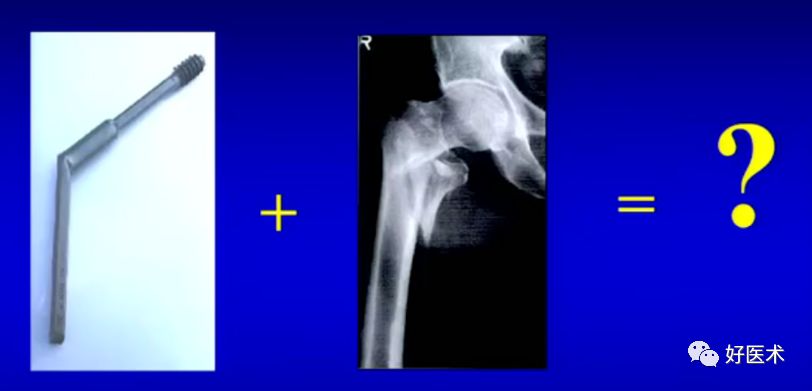

5.转子间骨折治疗的历史回顾

50年代后期A0推出95°/130°角钢板

-

60年代后流行动力髋部螺钉(DHS)

60年代后期 Kuntscher推出CC( Condy locephalic)钉

70年代出现 Ender钉

80年代开始逐步使用交锁髓内钉治疗

90年代后期出现 Gamma nail和PFN

现在发展:Gamma3和PFNA、 Trigen InterTAN等